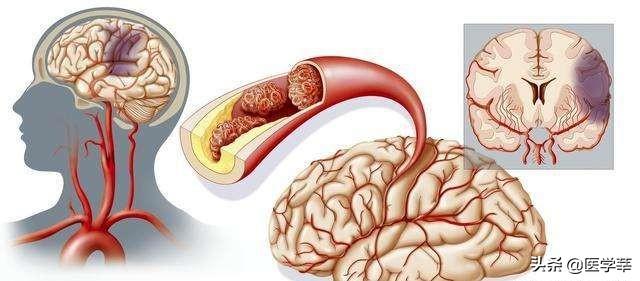

Notre cerveau gère presque toutes les fonctions de notre corps et est connu comme le commandant du corps. Le cerveau dépend du sang pour transporter l'oxygène et les nutriments dont il a besoin. Lorsque les vaisseaux sanguins sont bloqués pour diverses raisons, le cerveau est incapable d'obtenir de l'oxygène et des nutriments et meurt, entraînant la perte de fonctions de notre corps, ce qui est appelé infarctus cérébral. Les fonctions des différentes parties du cerveau étant différentes, les patients auront des séquelles plus ou moins importantes selon la localisation et l'étendue de la nécrose. Certaines personnes peuvent n'avoir qu'un léger vertige et découvrir qu'elles ont subi un infarctus cérébral lorsqu'elles se rendent à l'hôpital pour un examen (la plupart des patients atteints d'infarctus cérébral lacunaire sont découverts au cours de l'examen). Certains patients garderont des séquelles telles que l'hémiplégie, l'immobilité, la cécité, le retard mental, voire la mort.

L'infarctus cérébral est en fait un trouble de l'irrigation sanguine des vaisseaux sanguins du cerveau, qui se traduit par une irrigation sanguine insuffisante du cerveau, ce qui déclenche l'ischémie et l'hypoxie et aggrave encore la nécrose ischémique ou le ramollissement du tissu cérébral. L'infarctus cérébral représente la majorité des accidents vasculaires cérébraux dans la pratique clinique, et les types d'accidents vasculaires cérébraux les plus courants sont les suivantsThrombose cérébrale, infarctus lacunaire et embolie cérébraleetc.

L'infarctus cérébral est divisé en plusieurs types en fonction des différentes causes de l'infarctus : la rupture de la plaque causée par l'athérosclérose, formant un thrombus qui bloque les vaisseaux sanguins cérébraux, forme un infarctus cérébral ; l'embolie formée dans la région du cœur en raison d'une fibrillation auriculaire, d'un flutter auriculaire, d'une insuffisance cardiaque, d'une maladie valvulaire cardiaque, etc., qui pénètre dans les vaisseaux sanguins cérébraux avec le flux sanguin pour bloquer les vaisseaux sanguins cérébraux, forme également un infarctus cérébral ; l'occlusion des petits vaisseaux sanguins des artères cérébrales en raison d'un durcissement et de lésions, etc. forme également un infarctus cérébral, et ces infarctus cérébraux se produisent lentement en termes de pathogenèse. Ces infarctus cérébraux, bien qu'ils soient lents à se produire, mais lorsque les vaisseaux sanguins cérébraux sont soudainement bloqués, en particulier les vaisseaux sanguins importants responsables de l'approvisionnement en sang du cerveau, l'infarctus cérébral se produit d'un seul coup et il n'y a pas trop de précurseurs pour que nous puissions y faire face. L'infarctus cérébral se produit directement lorsqu'il entraîne directement dans le corps une hémiplégie, une aphasie, une ataxie, qui peuvent être accompagnées de maux de tête sévères, de nausées, de vomissements et d'autres symptômes, et l'état peut rapidement évoluer vers un infarctus cérébral. Par conséquent, pour prévenir l'infarctus cérébral, nous devrions toujours contrôler activement le risque à partir de la pathogenèse, et l'idée de se fier aux précurseurs ou aux symptômes précoces pour juger du risque d'infarctus cérébral est très difficile à mettre en œuvre pour prévenir le risque et intervenir à l'avance.

L'infarctus cérébral est également appeléInfarctus cérébral ou accident vasculaire cérébral ischémique (AVC ischémique cérébral)Ce terme désigne la nécrose ou le ramollissement du tissu cérébral dû à un manque d'apport sanguin au cerveau, qui se produit à la suite d'une ischémie ou d'une hypoxie.

L'aura de l'infarctus cérébral apparaît dans les jours ou les mois qui précèdent la survenue de l'infarctus cérébral, à ce moment-là, les artères de la tête et du cou ne sont pas encore complètement bloquées, ou bien, bien qu'elles soient bloquées, dans un laps de temps relativement court, par autolyse, auto-passage pour augmenter ou restaurer l'apport sanguin au tissu cérébral, n'a pas causé d'ischémie, d'hypoxie et de nécrose du tissu cérébral, cette aura est connue sous le nom d'accident ischémique transitoire. L'accident ischémique transitoire et l'infarctus cérébral présentent des symptômes similaires, tels qu'une faiblesse unilatérale d'un membre, des anomalies sensorielles, des troubles du champ visuel, un engourdissement du visage, des cornes tordues de la bouche, une paralysie de la langue, etc., qui sont causés par l'obstruction du système de l'artère carotide interne, qui fournit les 2/3 de l'apport sanguin au cerveau ; et des symptômes tels que le vertige, les troubles de l'équilibre, la diplopie, etc., qui sont causés par l'obstruction du système de l'artère vertébrale basilaire, qui fournit 1/3 de l'apport sanguin au cerveau. La différence est que les accidents ischémiques transitoires sont plus courts, avec une durée médiane de 14 minutes pour le blocage du système de l'artère carotide interne et de 8 minutes pour le blocage du système de l'artère vertébrale basilaire, et qu'ils ne durent généralement pas plus d'une heure et pas plus de 24 heures, alors que les symptômes de l'infarctus cérébral peuvent durer plus de 24 heures et sont persistants.